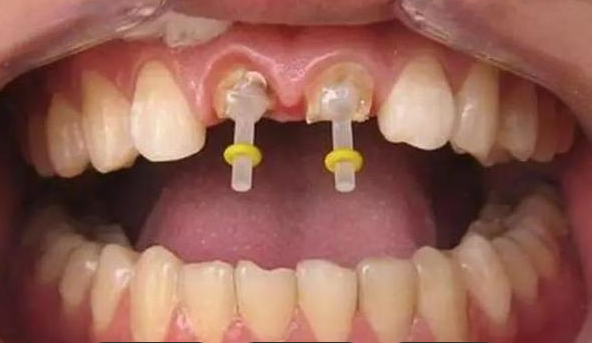

桩核冠与全冠修复

桩核冠则是先制作一个桩核,然后再取模制作牙冠,这种方法通常需要更多的就诊次数。在材料选择上,桩核和桩冠可以根据具体情况选用金属、瓷或纤维等不同材料,每种材料都有其优缺点,如金属桩强度高但弹性差,纤维桩弹性好但可能不适合所有病例。